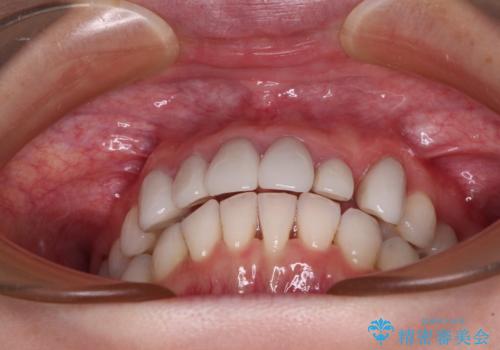

前歯のデコボコと奥歯の咬み合わせをインビザラインで改善

- 上下前歯のデコボコと奥歯の欠損を気にして来院された患者様です。

右下の欠損分は奥歯が倒れ込んでスペースがなくなっていたため、矯正治療により本来の位置に歯を移動させ、オールセラミックブリッジによる欠損補綴治療を行うこととしました。

全顎的にセラミッククラウンが多く装着されているため、インビザラインによる矯正治療を行うこととしました。

右下は移動量が多いため、十分な移動が達成されない場合はワイヤー装置を使用する予定としておりましたが、しっかりとマウスピースを装着してくださったため、前歯とともに十分に歯を動かすことができました。